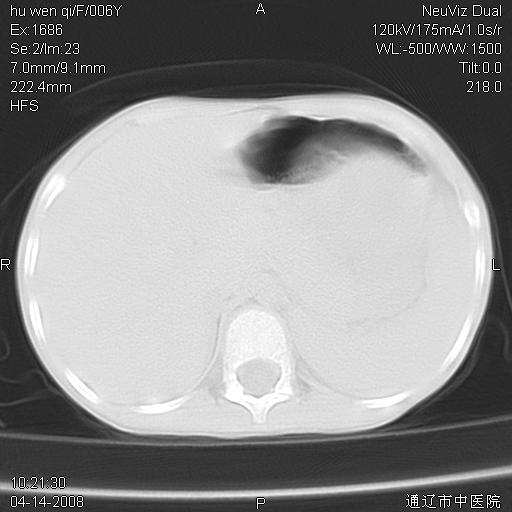

女, 6岁 ,反复咳嗽2周,近两日发热伴右侧胸痛

两肺多发似葡萄状大小不等高密度区,边界清楚,部分见薄壁空洞。左胸壁后方见局限性高密度区,边界清楚,广基与后侧胸壁相连。

考虑:1、金黄色葡萄球肺炎(血源性);

2、左侧包裹性积液;

两肺多发似葡萄状大小不等高密度影,边界清楚,部分见薄壁空洞。左胸壁后方见局限性高密度区,边界清楚,广基与后侧胸壁相连。另示:脾大

2 肺包囊虫病

3、左侧包裹性积液;

两肺多发结节状高密度阴影,边界清楚,部分见薄壁空洞,双侧叶间包裹积液;脾大。可能诊断:1、机遇性感染,肺努卡氏菌病;2、血源性葡萄球肺炎

左肺下叶肿块伴双肺多发大小不一结节。考虑血源性金黄色葡萄球肺炎。

谢谢各位的诊断意见,结果已经出来了,是神经母细胞瘤肺转移,原发病灶在肾,现在已进行放、化疗。